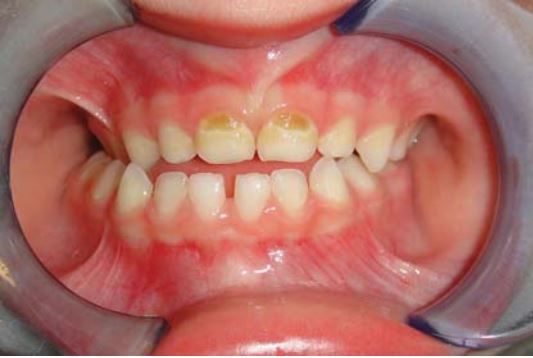

Sealant giúp ngăn ngừa sâu hố rãnh ở răng cối vĩnh viễn ở trẻ. Răng cối vĩnh viễn mới mọc thường xốp và dễ bị sâu. Men răng trưởng thành sau 62 tháng kể từ khi mọc. Trám sealant càng sớm càng giúp giảm tỉ lệ sâu hố rãnh. Nguy cơ sâu răng cao nhất là trong năm đầu tiên kể từ khi mọc răng.

Răng mọc lên chưa hoàn toàn

Trám sealant cho những răng này thường khó vì khó cách li, do đó khuyến cáo trám bằng các vật liệu ưa nước như GIC hoặc sealant GIC (Vitrebond). Răng được theo dõi liên tục cho đến khi mọc lên hoàn toàn, lúc đó sẽ thay lớp GIC bằng sealant.